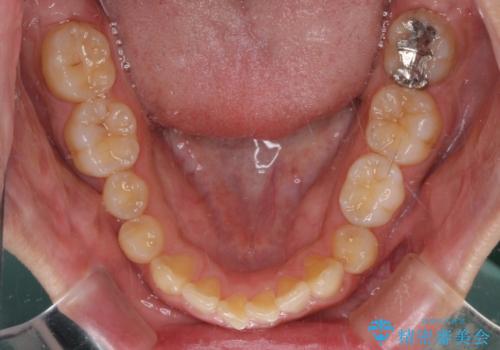

- 前歯の隙間を気にして来院された患者様です。

下顎前歯が見えなくなるくらいに深い咬み合わせであり、さらに上顎の正中が開くほど下の前歯が突き上げている状態でした。

奥歯は手前に倒れてしまっているため、後方に起き上がらせることで深い咬み合わせ・ディープバイトを改善する必要があります。